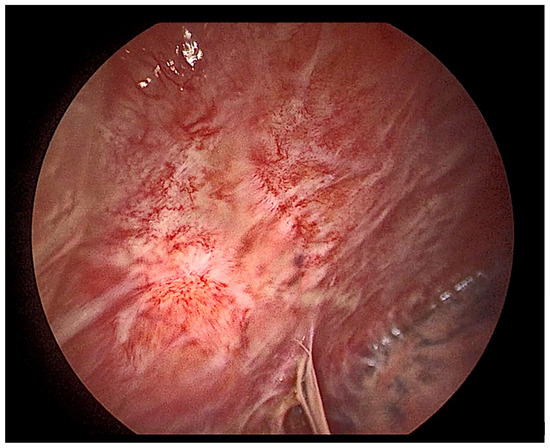

- Ellayeh, M.; Bedawi, E.; Banka, R.; Sundaralingam, A.; George, V.; Kanellakis, N.; Hallifax, R.; Abdelwahab, H.; Rezk, N.; Hewidy, A.; et al. Objective Thoracoscopic Criteria in Differentiation between Benign and Malignant Pleural Effusions. Respiration 2021, 101, 46–56. [Google Scholar] [CrossRef]